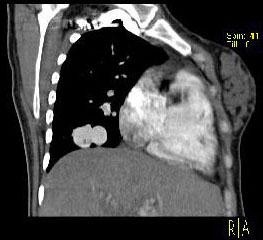

问题 男性,26岁,头晕、气逼三年余,CT检查如图所示,请选择的最可能诊断 ( )

选项 A、动静脉畸形 B、动脉瘤 C、毛细血管扩张症 D、毛细血管瘤 E、海绵状血管瘤

答案 A